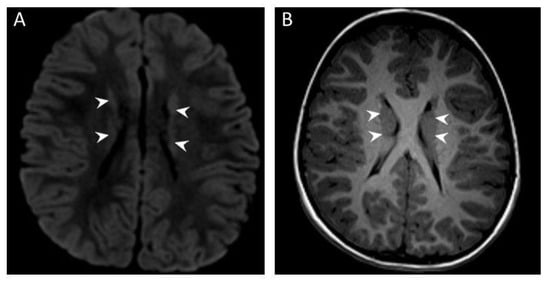

3.2. Brain MRI Results